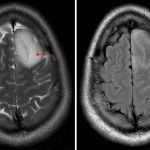

- T1 hypointense, T2 hyperintense expansile mass extending to the cortex in the left superior frontal gyrus

- Mixed hyperintense and isointense internal FLAIR signal

- No corresponding enhancement, restricted diffusion, or susceptibility artifact

- Mild corresponding local mass effect without midline shift or evidence of herniation or hydrocephalus

IDH-mutant astrocytoma

- Dysembryoplastic neuroepithelial tumor (DNET) – This case is actually a very good look for a DNET, specifically bubbly internal T2 signal hyperintensity, signal suppression on FLAIR, and lack of contrast enhancement. DNETs are often smaller than the tumor in this case

- Oligodendroglioma – These tumors may also be peripheral, they commonly calcify, and they sometimes enhance. The T2-FLAIR mismatch sign (hyperintense T2 signal contrasted with iso- or hypointense FLAIR signal) is typical for 1p19q intact astrocytomas, but NOT typical for oligodendrogliomas

- The T2-FLAIR mismatch sign can be seen with both astrocytomas and DNETs, but is not typical for oligodendrogliomas